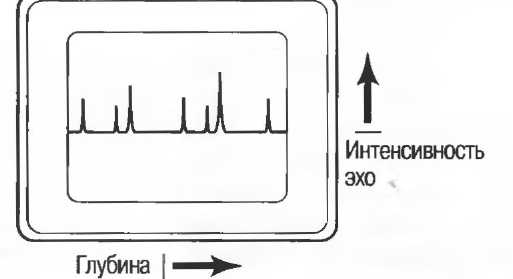

1. А-режим. При работе в А-режиме отраженные сигналы изображаются в виде пиков, при этом можно измерить расстояние между двумя различными структурами (рис. 1а). Сама структура в этом режиме не изображается, однако подобный принцип используется и при получении двухмерного изображения.

Рис. 1а. Срез в А-режиме: расположение пиков показывает глубину расположения отражающей структуры. Высота пика определяет интенсивность отраженного сигнала.